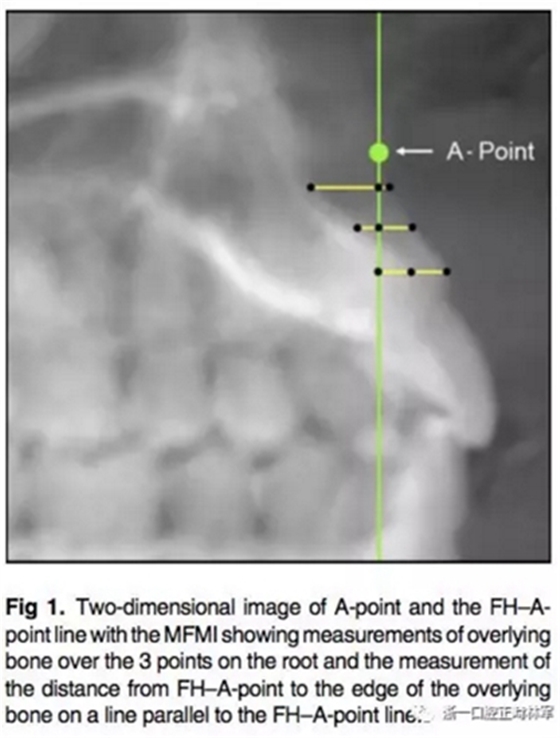

所有圖像導(dǎo)入Dolphin軟件中進行處理,2D側(cè)位圖像為使用Dolphin軟件使用相同的標準切割CBCT獲得。使用眶耳平面(FH)作為水平參考平面,使用垂直于眶耳平面(FH)同時通過A點的直線作為垂直參考平面。在上切牙最前點進行定點,牙根分界為自釉牙骨質(zhì)界至根尖,在牙根根尖、牙長1/2處、釉牙骨質(zhì)界下3mm處進行定點。使用FH的平行線測量頰側(cè)牙槽骨至牙根上3點的距離,同時測量A點與以上三條線段的距離,如圖所示。測量切牙的轉(zhuǎn)矩,使用通過切點、根尖的直線與FH平面的所成角。

在CBCT的3D圖像上使用右側(cè)耳點與眶下點定FH平面。同樣定好過A點與FH垂直的垂直參考線,測量牙根上點至垂直參考線的距離。

根據(jù)每顆切牙相對上頜骨的位置在同一平行切面上各自確定A點,定好切牙最前點(MFMI),牙根長度依然為釉牙骨質(zhì)界至根尖點。使用與2D側(cè)位片上相同的方法進行牙根至骨皮質(zhì)的測量。轉(zhuǎn)矩的測量也同2D側(cè)位片。